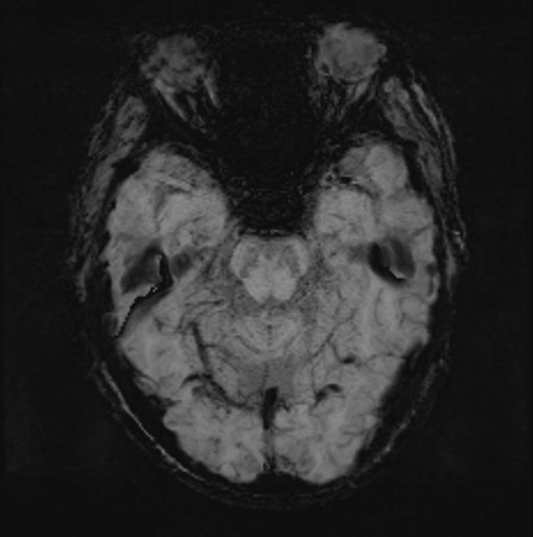

辅助检查:入院后抽血常规检查未见异常。头颅磁共振未见明显中脑、脑桥、小脑萎缩,SWI提示双侧黑质燕尾征模糊。震颤图:静止时,右上肢拇短展肌、食指伸肌、指总伸肌、小指展肌可见5Hz震颤群放电活动;左下肢胫前肌、腓骨长肌、腓肠肌可见4Hz震颤群放电活动。